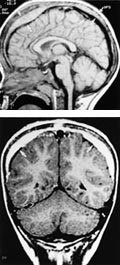

Selv i forhold til moderne spiral-CT er MR-undersøkelse helt overlegen, spesielt ved diagnostikk relatert til bakre skallegrop og spinalkanal. Ved siden av vanlige spinnekkosekvenser, som gir god anatomisk kartlegging og vevskarakteristikk, benyttes for barn inntil 18 måneder spesielle sekvenser med lang repetisjonstid for å øke kontrasten mellom normalt og unormalt hjernevev (6). Fremstillingen av myeliniseringsprosessen og små fokale lesjoner forbedres med inversjonsgjenvinningssekvens (inversion recovery). Myeliniseringen begynner in utero og fortsetter etter fødselen. Ved to års alder har hjernen oppnådd nærmest voksent myeliniseringsmønster. Deponeringen av myelin, som er et hydrofobt glukoprotein, kan følges med MR. Forsinket eller unormal myelinisering er et viktig funn, da det kan avspeile enten svikt i myelindanningen, nedbrytning av normalt myelin (demyelinisering) eller produksjon av defekt myelin (dysmyelinisering). Andre sekvenser kan benyttes for å få frem differensieringen mellom grå og hvit substans, komplekse malformasjoner, tumorer og kar.

Medfødte misdannelser opptrer hyppig i sentralnervesystemet. Enhver sykdomsepisode som skader hjernen i vekst (iskemisk, metabolsk, toksisk eller infeksiøs), kan forårsake misdannelser. En forstyrrelse av de migrerende nevroblastene tidlig i svangerskapet resulterer i anomalier av ulik alvorlighetsgrad som agyri, pakygyri, schizencefali, polymikrogyri og heterotopisk grå substans (7). Klinisk kan disse anomaliene føre til for eksempel psykomotorisk retardasjon, epilepsi og cerebral parese. Agenesi av corpus callosum, Arnold-Chiaris malformasjoner og Dandy-Walkers kompleks er andre eksempler på alvorlige utviklingsforstyrrelser. En fullstendig utredning av barn med alvorlige nevrologiske symptomer forutsetter kartlegging med MR.

Utredning av spinalkanalen gjøres vanligvis med sagittale og transversale snitt. Ved dysrafi, tumor, infeksjon og betennelse gis kontrast. Utviklingsanomalier er knyttet til danningen av nevralrøret og separasjonen av de forskjellige embryonale lagene. Spinal dysrafi, myelo-, meningo- og myelomeningocele, syringomyeli, intraspinalt lipom og diastematomyeli er eksempler på slike anomalier. MR gir mulighet for en nøyaktig og detaljert fremstilling av de anatomiske forholdene (fig 1), noe som selvfølgelig er av avgjørende betydning før kirurgisk korreksjon. MR spiller en helt avgjørende rolle innen pediatrisk nevroradiologi.